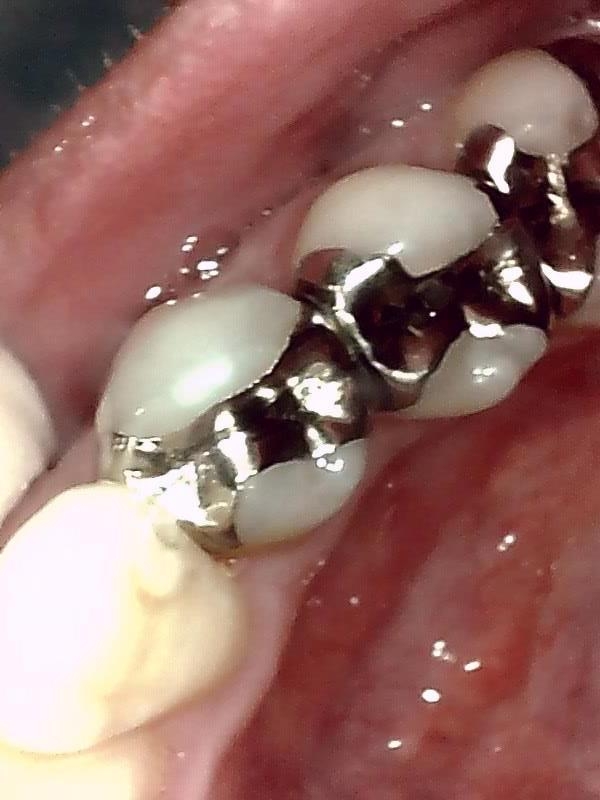

部位:右下8番埋伏歯

切開 歯肉剝離

歯肉を切開し、歯が見えるようにして、

周辺の骨を削らないように親知らずを分割し抜きやすくしていきます。

この抜歯法により術後の腫れ痛みが大幅に軽減されます。

抜歯窩

縫合

当院では、傷口は最小限に、骨は極力削らずに行います。

骨が歯を覆っているケース以外は骨を削ることはありません。

親知らずのみにアプローチし歯を分割し最小限の傷口で取り出します。